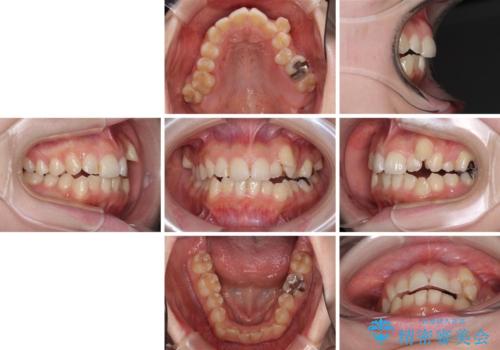

- 顕著な八重歯など、上下前歯のデコボコとスペースを気にして来院された患者様です。

八重歯改善には第一小臼歯の抜歯が必要であり、移動量が多いことから補助装置により八重歯を引き込むこととしました。

インビザラインでの治療をご希望であったので、インビザラインにて行うこととしましたが、右側前歯の改善にはワイヤー矯正が必要となる可能性があることをお伝えした上で治療を開始しました。